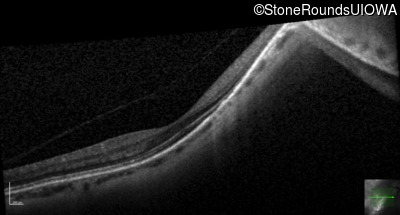

Age at visit: 41 years (Visit 2)

OD OS

This 41 year old woman was highly myopic as a child and experienced a rhegmatogenous retinal detachment OS at age 20.

Refraction OD:     -17.25 +1.00 x 93

Refraction OS:     -18.25 +3.50 x 56

The clinical features favoring the diagnosis of Sticker syndrome in this patient include extensive radial lattice degeneration, a personal and family history of rhegmatogenous retinal detachment, a history of cataract surgery before age 30 (and very high myopia before that), arthritis in her knees and hips and a slightly flattened mid-face.